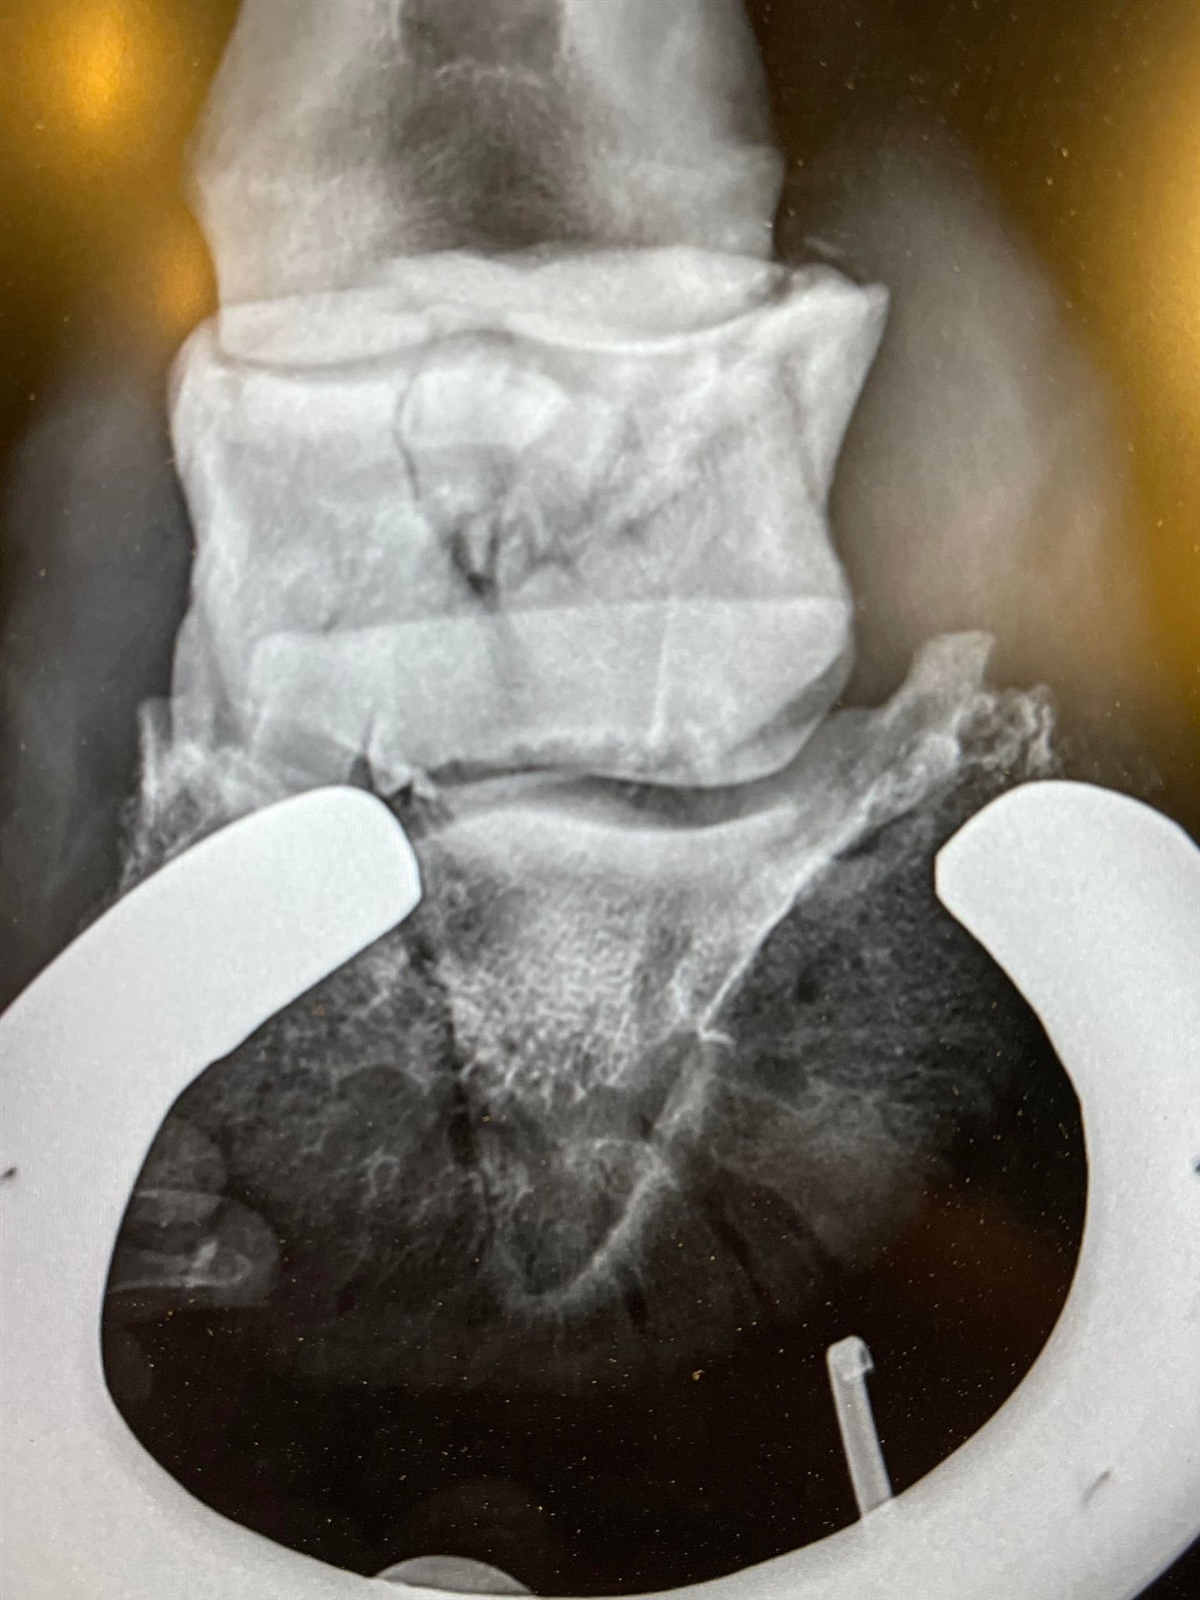

Hovbenet blev knust.